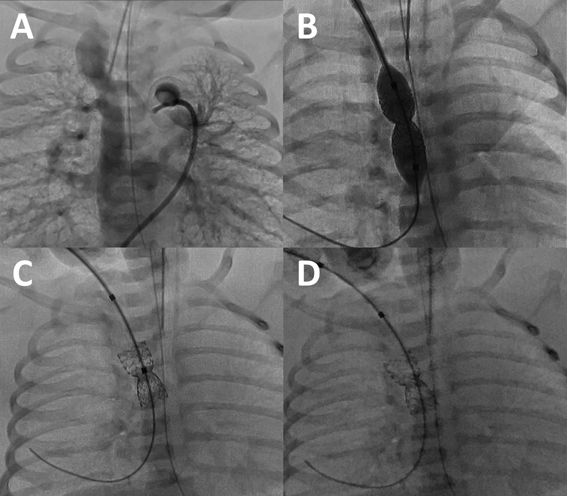

総肺静脈還流異常を合併した垂直静脈狭窄に対するステント留置中のバルーンエントラップメントEntrapment of a Balloon Catheter during Stent Implantation for Vertical Venous Stenosis in Two Neonates with Single Ventricle and Total Anomalous Pulmonary Venous Connection